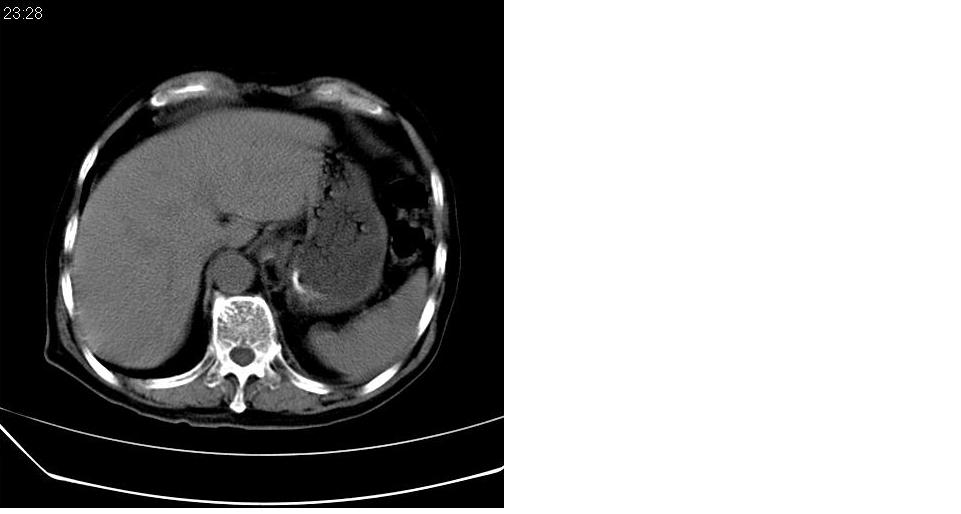

左下肺体积缩小,密度增高,见片增密影。边界模糊,见支气管充气像,肺门纵隔无异示,心脏气管左移,左侧胸腔少量积液。考虑肺部感染伴部分肺不张[有脑梗塞病史坠积性肺炎可能]

左肺下叶体积缩小,成类楔形软组织影,其内可见部分含气支气管影,相应左侧肺门区未见明显肿块,考虑炎性病变,建议抗炎后短期复查

左下肺体积缩小,密度增高,并见大片状致密影,边界模糊,其内见支气管充气像,肺门纵隔无异常,心脏气管左移,左侧胸腔少量积液。考虑:左肺炎性病变伴不张。

左肺下叶感染,肺膨胀不全,左胸腔积液,不能排除结核性病变